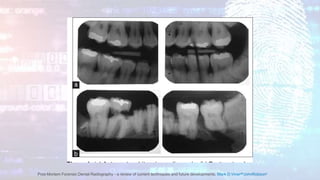

Dental Identification

• Forensic odontology has long been an essential discipline in the post-

mortem identification of human remains, the determination

of the age of live subjects and in wider aspects of forensic

investigation.

Post-Mortem Forensic Dental Radiography - a review of current techniques and future developments, Mark D.VinerabJohnRobsonc

• Much of forensic dental identification is based upon the

comparison of one set of records with another.

• Aside from the documented dental records, casts and photographs,

radiographs and scans are one of the main sources of evidence.

Previous scans and radiographs can be compared with

contemporaneous images taken of the subject.

• In the identification of the deceased, these examinations will be

performed on the cadaver.